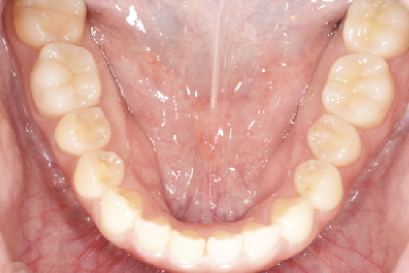

• 症例3

術前

*

術後

年代、性別

10代、女性

職業

学生

主訴

歯並び相談

部位

抜歯を併用してのインビザラインによる全顎矯正

治療期間

2年

矯正費用

95万円

施術説明

前歯が突出感と、下歯がガチャガチャしていることを改善したいということでした。マウスピース矯正は抜歯を伴う矯正は難しいという意見もありますが、適切に診査・診断を行い対応すれば問題ありません。本症例では、上下2本ずつ合計4本の抜歯を行い、スペースを作ることで、上記の問題を矯正で改善しました。非常に綺麗な歯並びになり、非常に喜んでもらえました。

副作用・リスク

なし